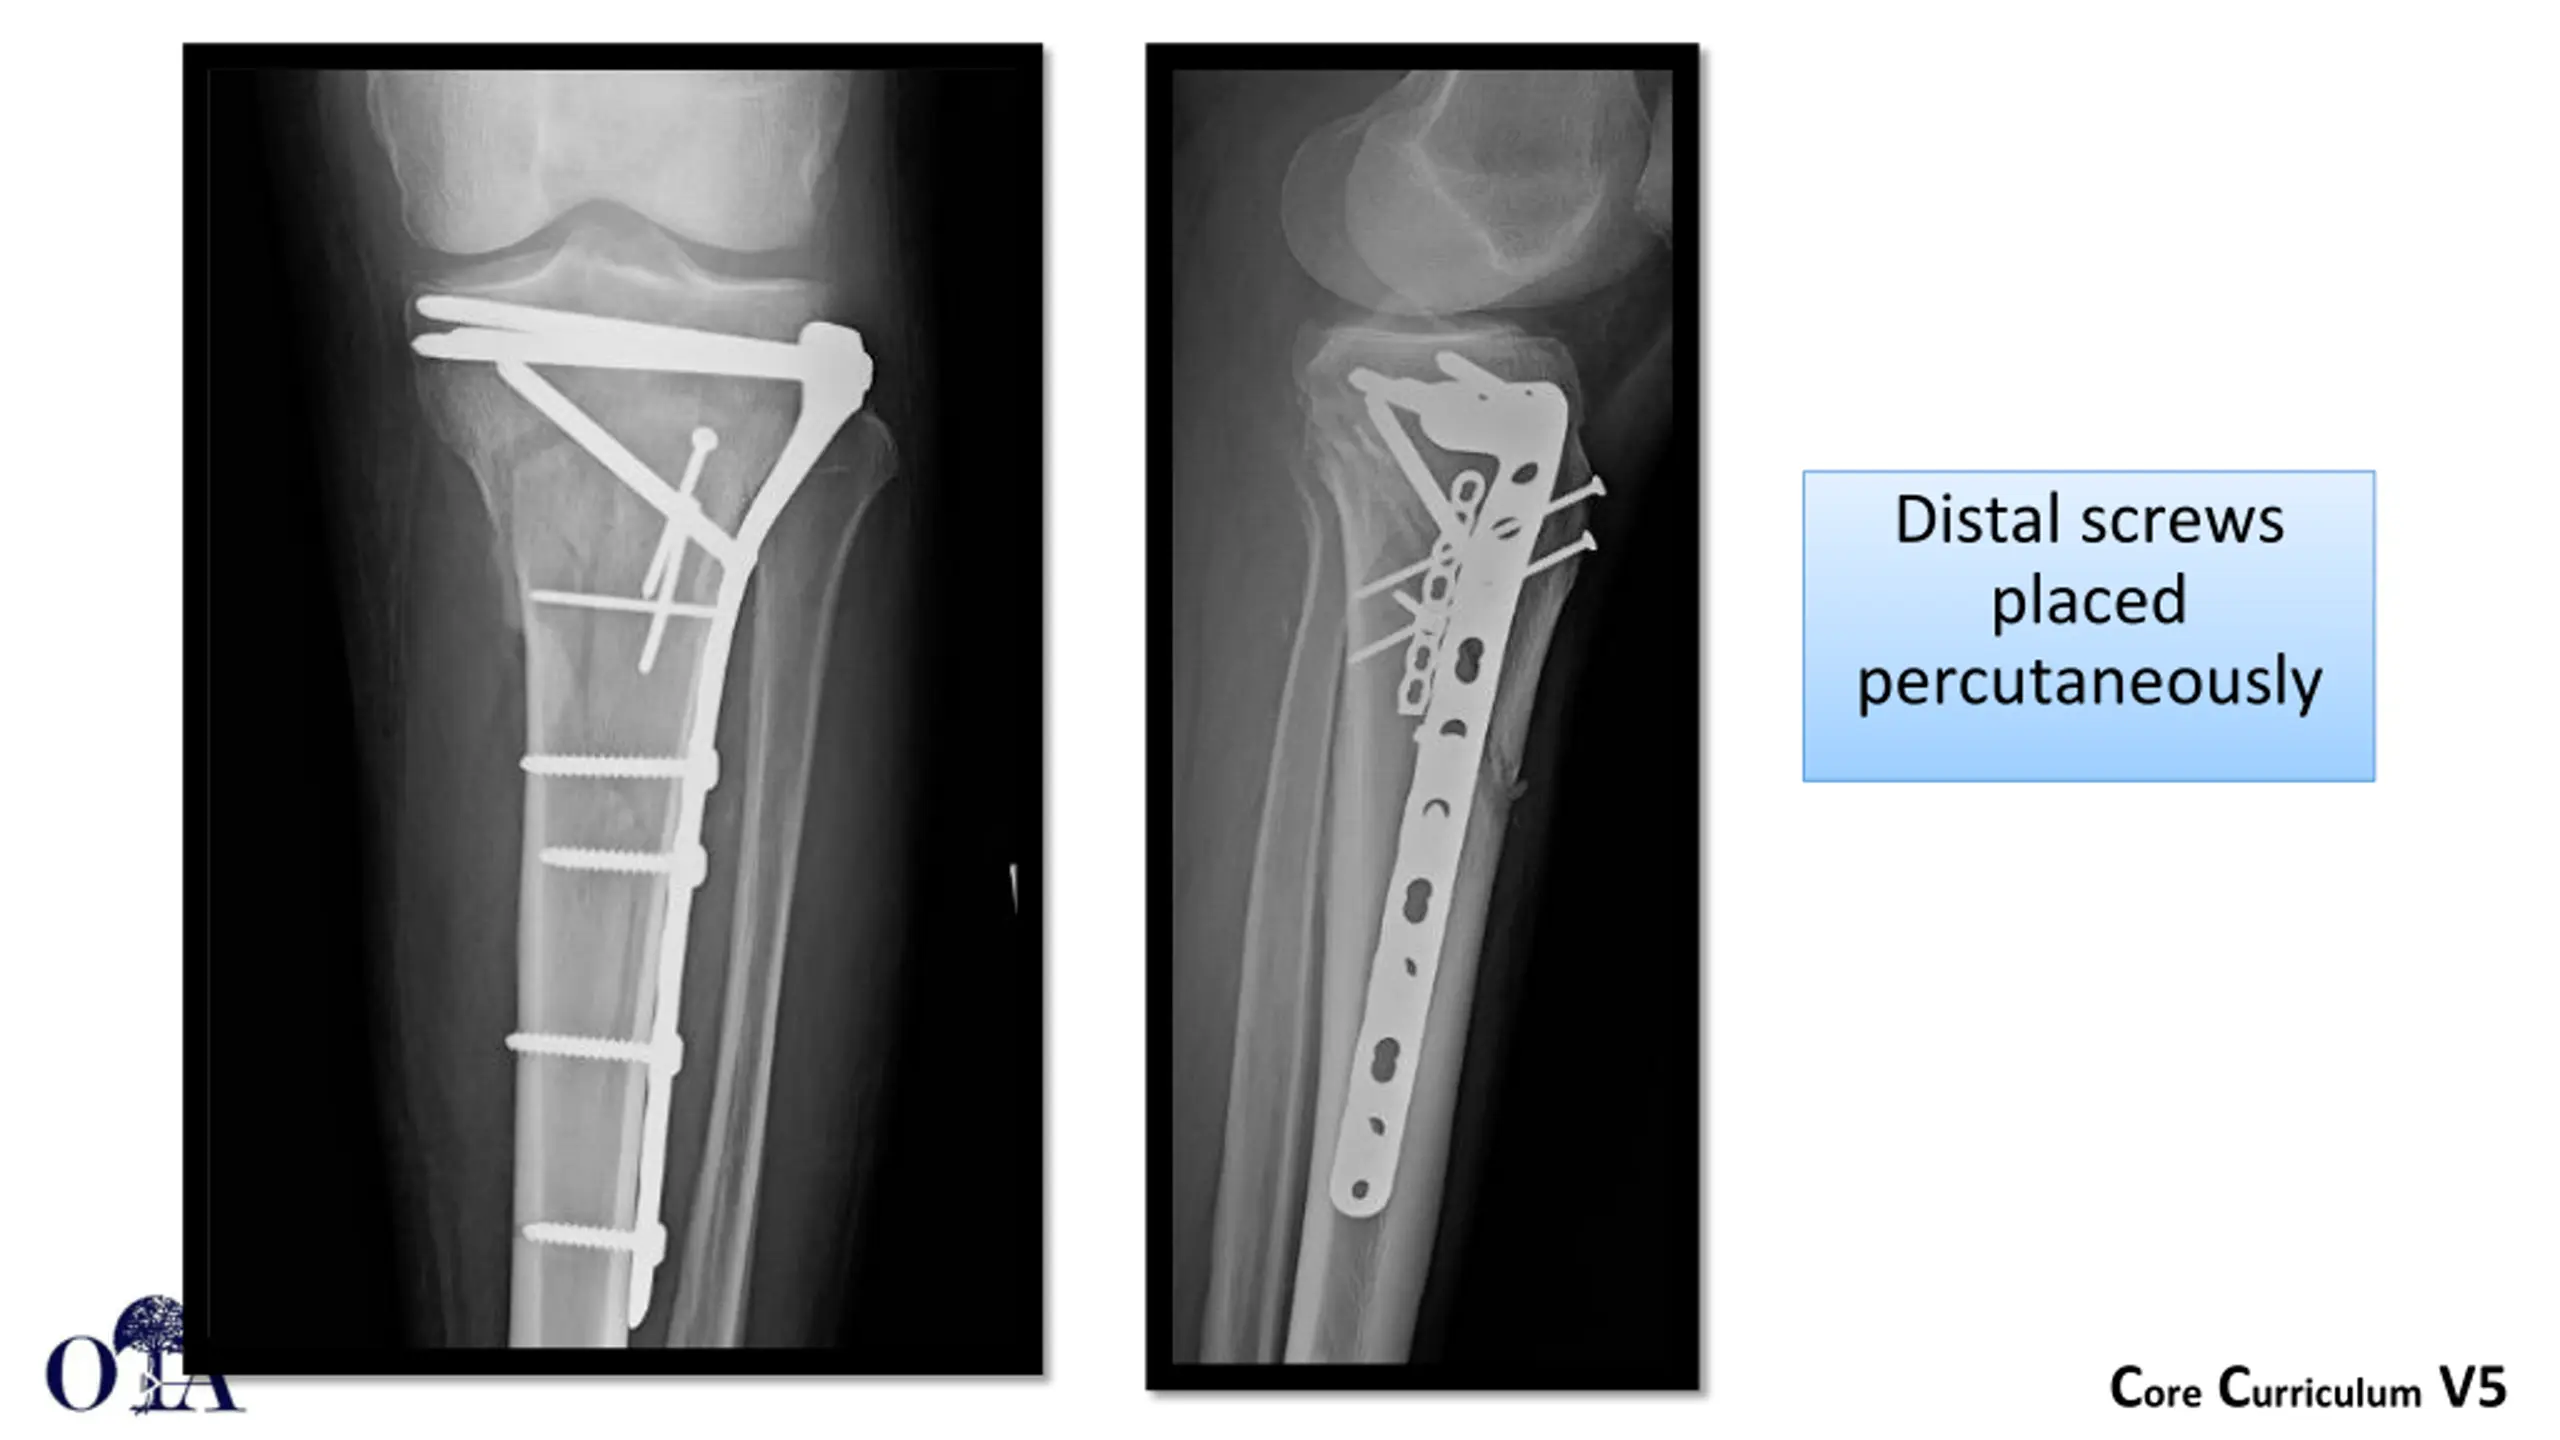

Distal screws placed percutaneously Core Curriculum V5